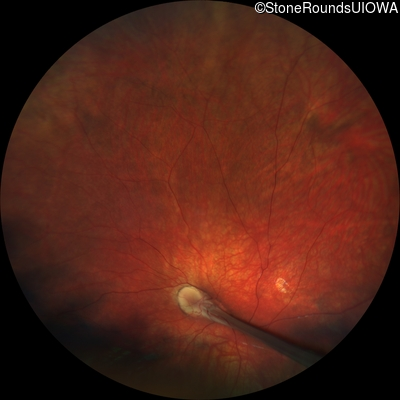

Visit at age: 2 years

Fundus Photography - Right - UCUSUM

Exemplar